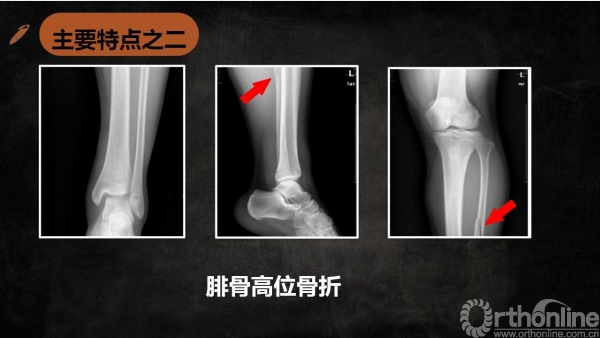

特殊类型的踝关节骨折——Maisonneuve骨折诊断与治疗

导语特殊类型踝关节骨折虽然临床少见,但是其诊断、治疗不准确会带来诸多不良后遗症,以致踝关节功能障碍,为了让大家更好的认识特殊类型的踝关节骨折,来自湖南师范大学附属岳阳医院(岳阳市二人民医院)的伍勇医生为我们带来系列文章,第一篇为Maisonneuve骨折诊断与治疗的介绍,请详见下文分解。